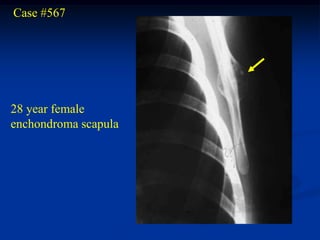

Case #567

28 year female

enchondroma scapula